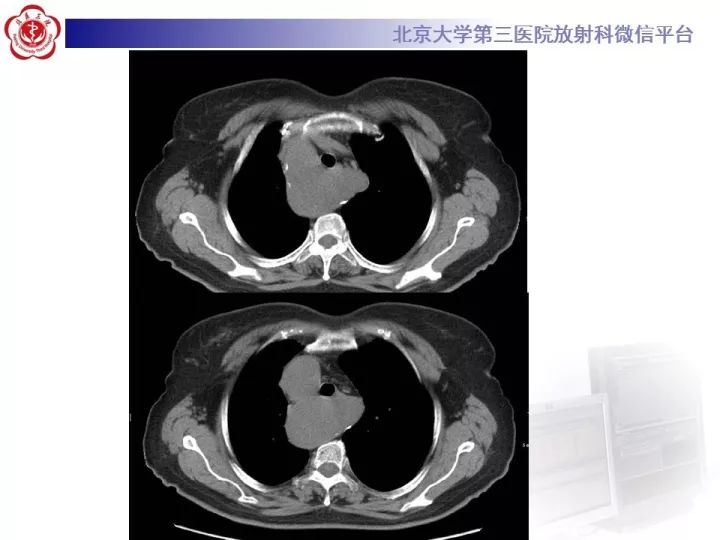

【病例】右位主动脉弓合并迷走左锁骨下动脉1例CT